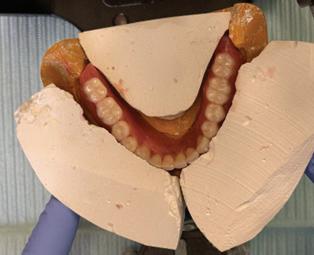

A special record base with ns was made and adapted to the mandibular master cast (Figure 3).

e record base shown in Figure 3 was adjusted in the patient's mouth to ensure stability and complete seating during opening, closing, swallowing and speaking.

A mixture of grey stick compound and cake wax were so ened and placed on the record base.

e base was inserted into the patient’s mouth, and she was instructed to repeat the motions of swallowing, pursing lips, and licking lips to facilitate accurate recording of the neutral zone as the impression material set (Figure 4).

e obtained neutral zone impression was positioned on the master cast, where location grooves were created. Mounting plaster was then applied along the labial and lingual surfaces to create an index from which the wax rim was molded to replicate the neutral zone (Figure 5).

Teeth arrangement was completed by verifying position against the plaster index to preserve the neutral zone (Figure 6).

Figure 3. Special record base with fins

Figure 4. Neutral zone recorded

Figure 5. Plaster index with lower record base

Figure 6. Teeth arrangement with plaster index